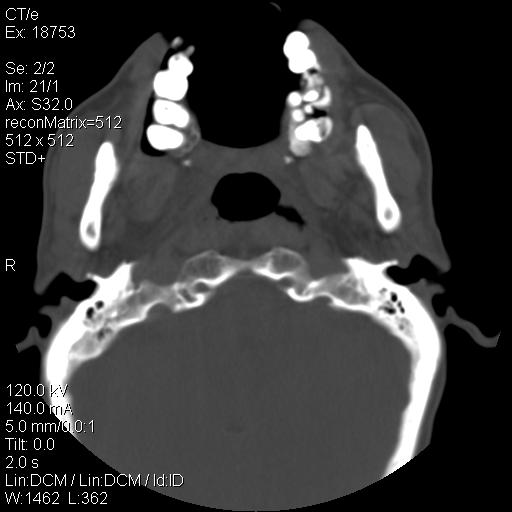

标题: CT21693:男 58岁 右侧咽部疼她2天余 PE:右侧扁桃体肿大 压痛 [打印本页]

标题: CT21693:男 58岁 右侧咽部疼她2天余 PE:右侧扁桃体肿大 压痛

喉部新生物,喉癌可能大,建议喉镜取组织活检。

考虑感染性病变可能性大,建议抗炎治疗后复查,必要时鼻咽腔镜活检排除占位。

右化脓性扁桃体炎症伴咽后壁脓肿形成.